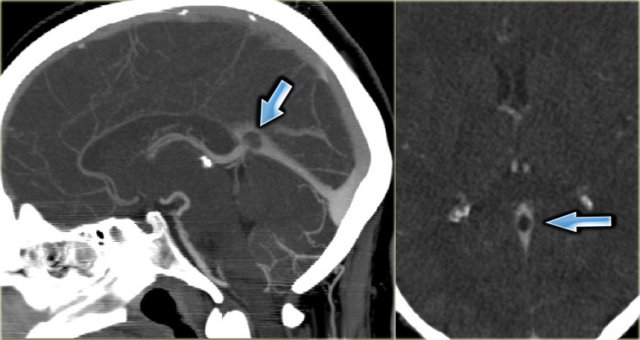

Empty delta sign

The empty delta sign is a finding that is seen on a contrast enhanced CT (CECT) and was first described in thrombosis of the superior sagittal sinus.

The sign consists of a triangular area of enhancement with a relatively low-attenuating center, which is the thrombosed sinus.

The likely explanation is enhancement of the rich dural venous collateral circulation surrounding the thrombosed sinus, producing the central region of low attenuation.

In early thrombosis the empty delta sign may be absent and you will have to rely on non-visualization of the thrombosed vein on the CECT.

The sign may be absent after two months due to recanalization within the thrombus.

Empty delta sign (2)

On the left a case of thrombosis of the right transverse sinus and the left transverse and sigmoid sinus (arrows).

There is enhancement surrounding the thrombosed hypoattenuating veins.